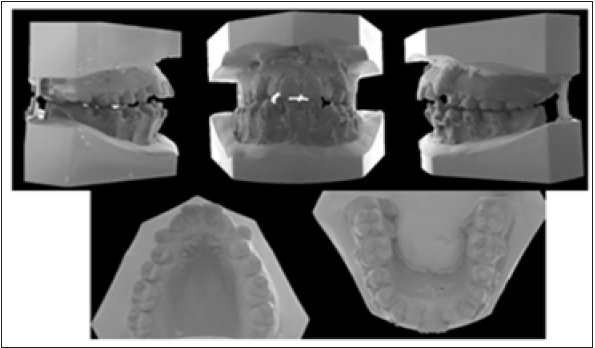

Hays nance and bolton analysis were done to define the space requirement (Figure 2). We need 9mm in the upper arch and 8,5 in the lower arch to relieve the crowding. The periodontal hygiene status was moderate. Panoramic radiography revealed no radiographic lesion or resorption around the roots (Figure 3). The pretreatment measurements showed, a class II skeletal relationship (ANB: 6.3). Maxillary (U1-SN: 115.1) and mandibular incisor inclinations (IMPA, L1-MP: 103.1) were out of normal limits (Figure 4) (Table 1). Based on these findings’ patient had skeletal class II bimaxillary retrognathia, dental class I molar and canine relationship, skeletal open bite with high angle-vertical growth pattern, increased upper incisor inclination, retrusive upper and lower soft tissue, crowding, gummy smile and convex profile.

Figure 2: Pretreatment dental casts.